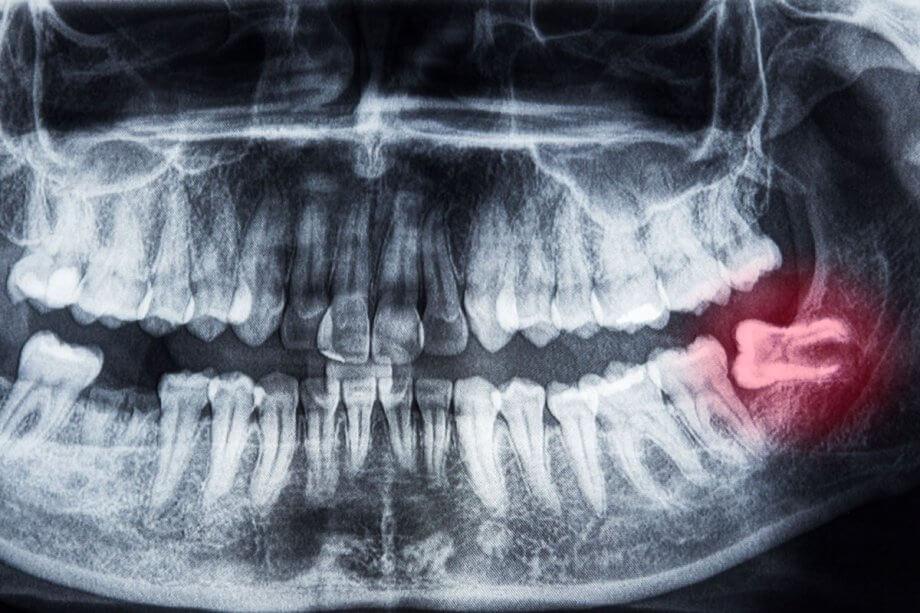

Kada su bolovi dugotrajni i jaki, vjerovatno je to zbog impaktiranog zuba. Umnjak može biti potpuno impaktiran, što znači da uopće ne može niknuti i zaglavljen je ispod tkiva desni, ili djelomično impaktiran, kada zub niče pod određenim uglom, a samo dio izlazi iz desni.

Postoji nekoliko razloga zbog kojih su impaktirani umnjaci toliko bolni. Prvo, činjenica da ne izbijaju vrši pritisak na vaše susjedne zube i uzrokuje bol u vilici. Ako se umnjaci ne izvade, to na kraju može rezultirati oštećenjem ostalih zuba.

Djelomično impaktirani umnjaci skloniji su kvarenju, jer ih je teško očistiti, kako zbog njihovog položaja u stražnjem dijelu usta, tako i zbog toga što se hrana i bakterije lako zaglave između tkiva desni i zuba. Impaktirani umnjaci također su skloniji infekciji, a ovo stanje se naziva perikoronitis. Inficirani umnjak može rezultirati ekstremnim bolom i zubnim apscesima, a u rijetkim slučajevima je čak moguće da se infekcija proširi i na druge dijelove tijela ako se ne liječi.